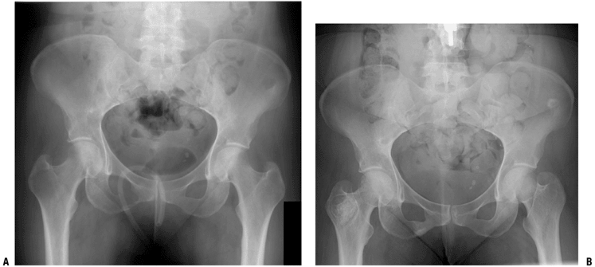

Figure 4.5-3 Anteroposterior view of pelvis in woman with a lytic metastatic breast cancer lesion in the right intertrochanteric region (A) responded well to radiotherapy, with a sclerotic healing response (B).